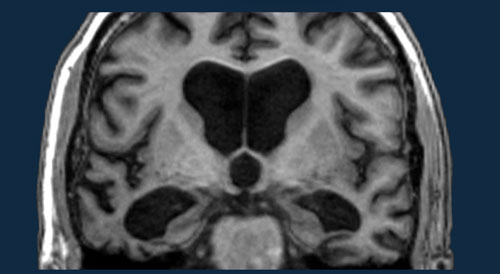

Dementia - Role of MRI